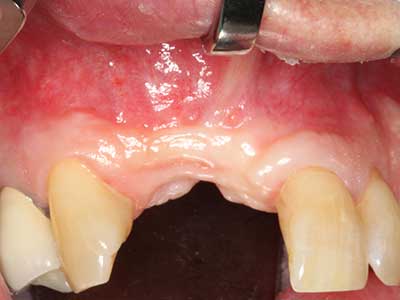

Indication: Periodontal therapy

Marginal periodontal diseases are the main reason for extractions in advanced age. These diseases are primarily caused by bacterial colonization of the gingival pocket, which causes inflammation followed by loss of the periodontium. The formation of subgingival biofilms and concrements is a significant aetiological factor for marginal bone atrophy, so their removal is an important part of the treatment (Drisko 2014, Plessas 2014).

Initial and surgical treatment phases are differentiated in the treatment of marginal periodontitis. In addition to instruction in oral hygiene and motivating patients, both phases should include adequate cleaning of the root surface. In the regenerative setting an open access is generally preferred. The root surface can be cleaned by piezo surgery using special attachments, where instruments with different curvatures are used to reach areas that are difficult to access, such as furcations. The integrated irrigation in the system flushes the detached concrements and bacteria out of the pocket. Specialized systems such as the Piezomed also include application feedback to minimize the ablation of hard dental substance. The greater the pressure on the periodontal attachment the greater the reduction in the amount of ablation.